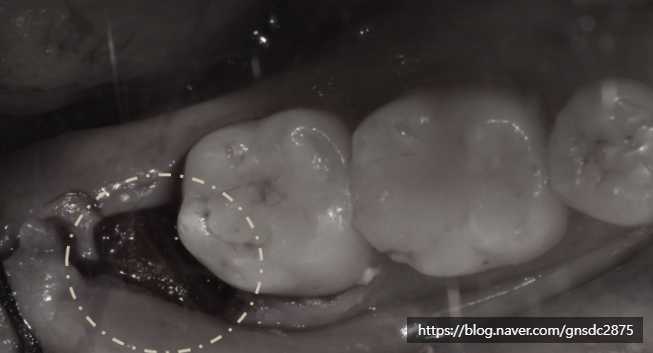

사랑니 발치 후 피덩이(혈병)

많은 분들이 빈공간 안에 있는

피딱지, 피덩이를 보고 떼어내야 하나 생각하십니다.

그러나 이 피덩이 또한 회복하는 과정 중

발치 후 초기에 자연스럽게 형성되는 혈병(혈전)으로,

출혈을 막고 상처를 보호하는 역할을 합니다.

피덩이(혈병)이 표시되어 있다.